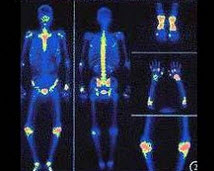

男性,43岁,1月前广泛前壁心梗,行溶栓治疗。行静息-硝酸甘油介入心肌显像如图,可能的诊断是()

A.左室心尖、间壁、部分前壁心梗

B.心梗区无存活心肌

C.左室外侧壁严重缺血

D.左室下后壁缺血

E.心尖心梗区有存活心肌